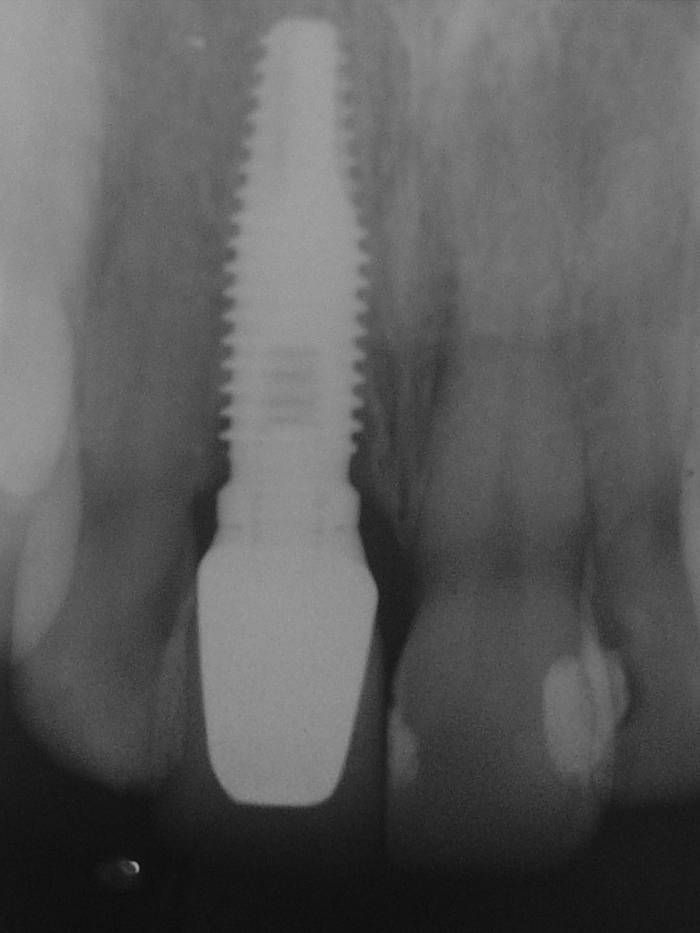

Raio X de controle realizado em agosto de 2013